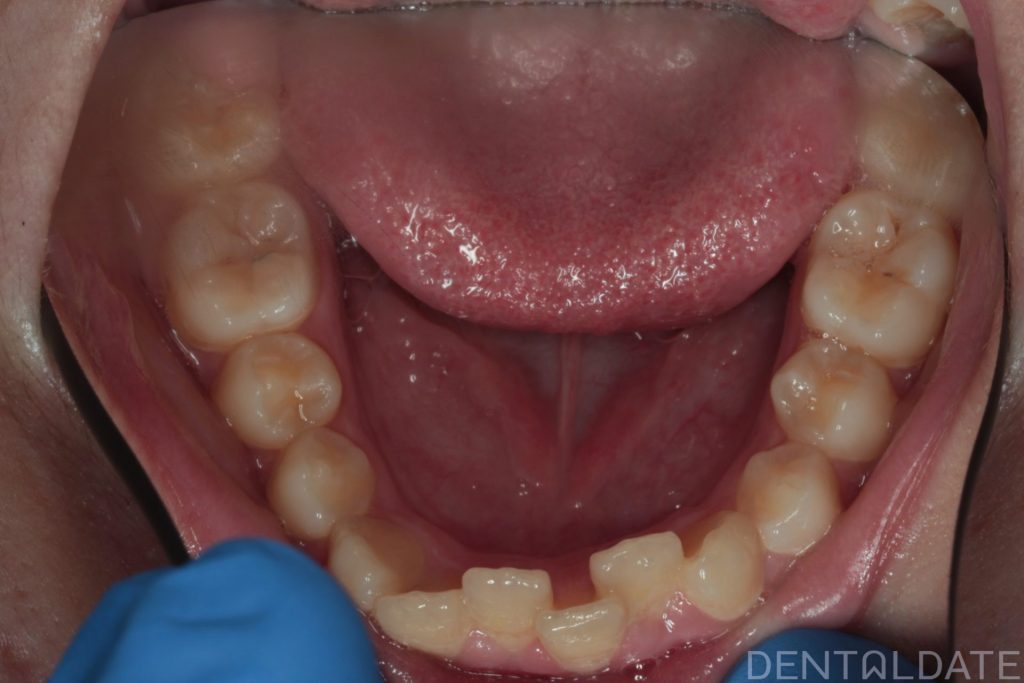

One tooth had erupted palatelly, with no space available for it in the dental arch.

The central aesthetic lines did not match, and the bite was incorrect.